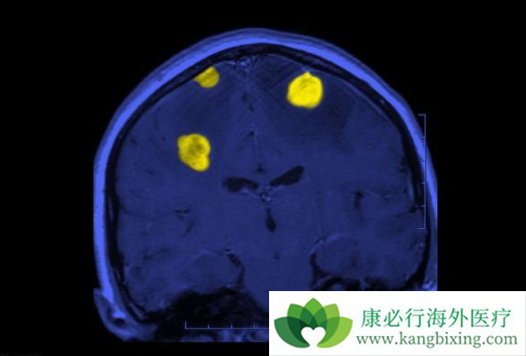

有些靶向药物的长期应用可导致神经系统的不良反应,虽然并不常见,但若发生时处理不当,可使患者留下神经系统后遗症甚至导致死亡,故应当引起足够的重视。可逆性后脑白质病综合征(RPLS)是VEGF抑制剂的一种少见但是十分严重的不良反应,最早见于贝伐单抗,发生率约为0.1%,其主要表现为头痛、癫痫发作、嗜睡、不同程度意识障碍及视觉异常。

治疗应去除病因,再对症处理,一旦经影像学确诊发生RPLS,应立即停药,再给予降压等对症治疗,一般会在数天内好转,此病预后良好。进行性多灶性白质脑病(PML)是一种亚急性脱髓鞘性疾病,常见于免疫系统功能受到严重抑制的患者,最常出现的症状为视觉障碍、肌无力和认知功能的改变,其致死率高,大部分患者在发病后3-6个月内死亡。

进行性多灶性白质脑病的发病率虽然较低,但由于其病情进展迅速,且目前尚无可靠的预防措施及有效的治疗方法,患者的预后往往极差。在利妥昔单抗的治疗过程中,如果患者出现神经症状,应考虑请神经科医师会诊,并进行相关检查。对于确诊为PML的患者,应停止使用利妥昔单抗,同时采取积极的抗病毒治疗,以尽早重建机体免疫系统。